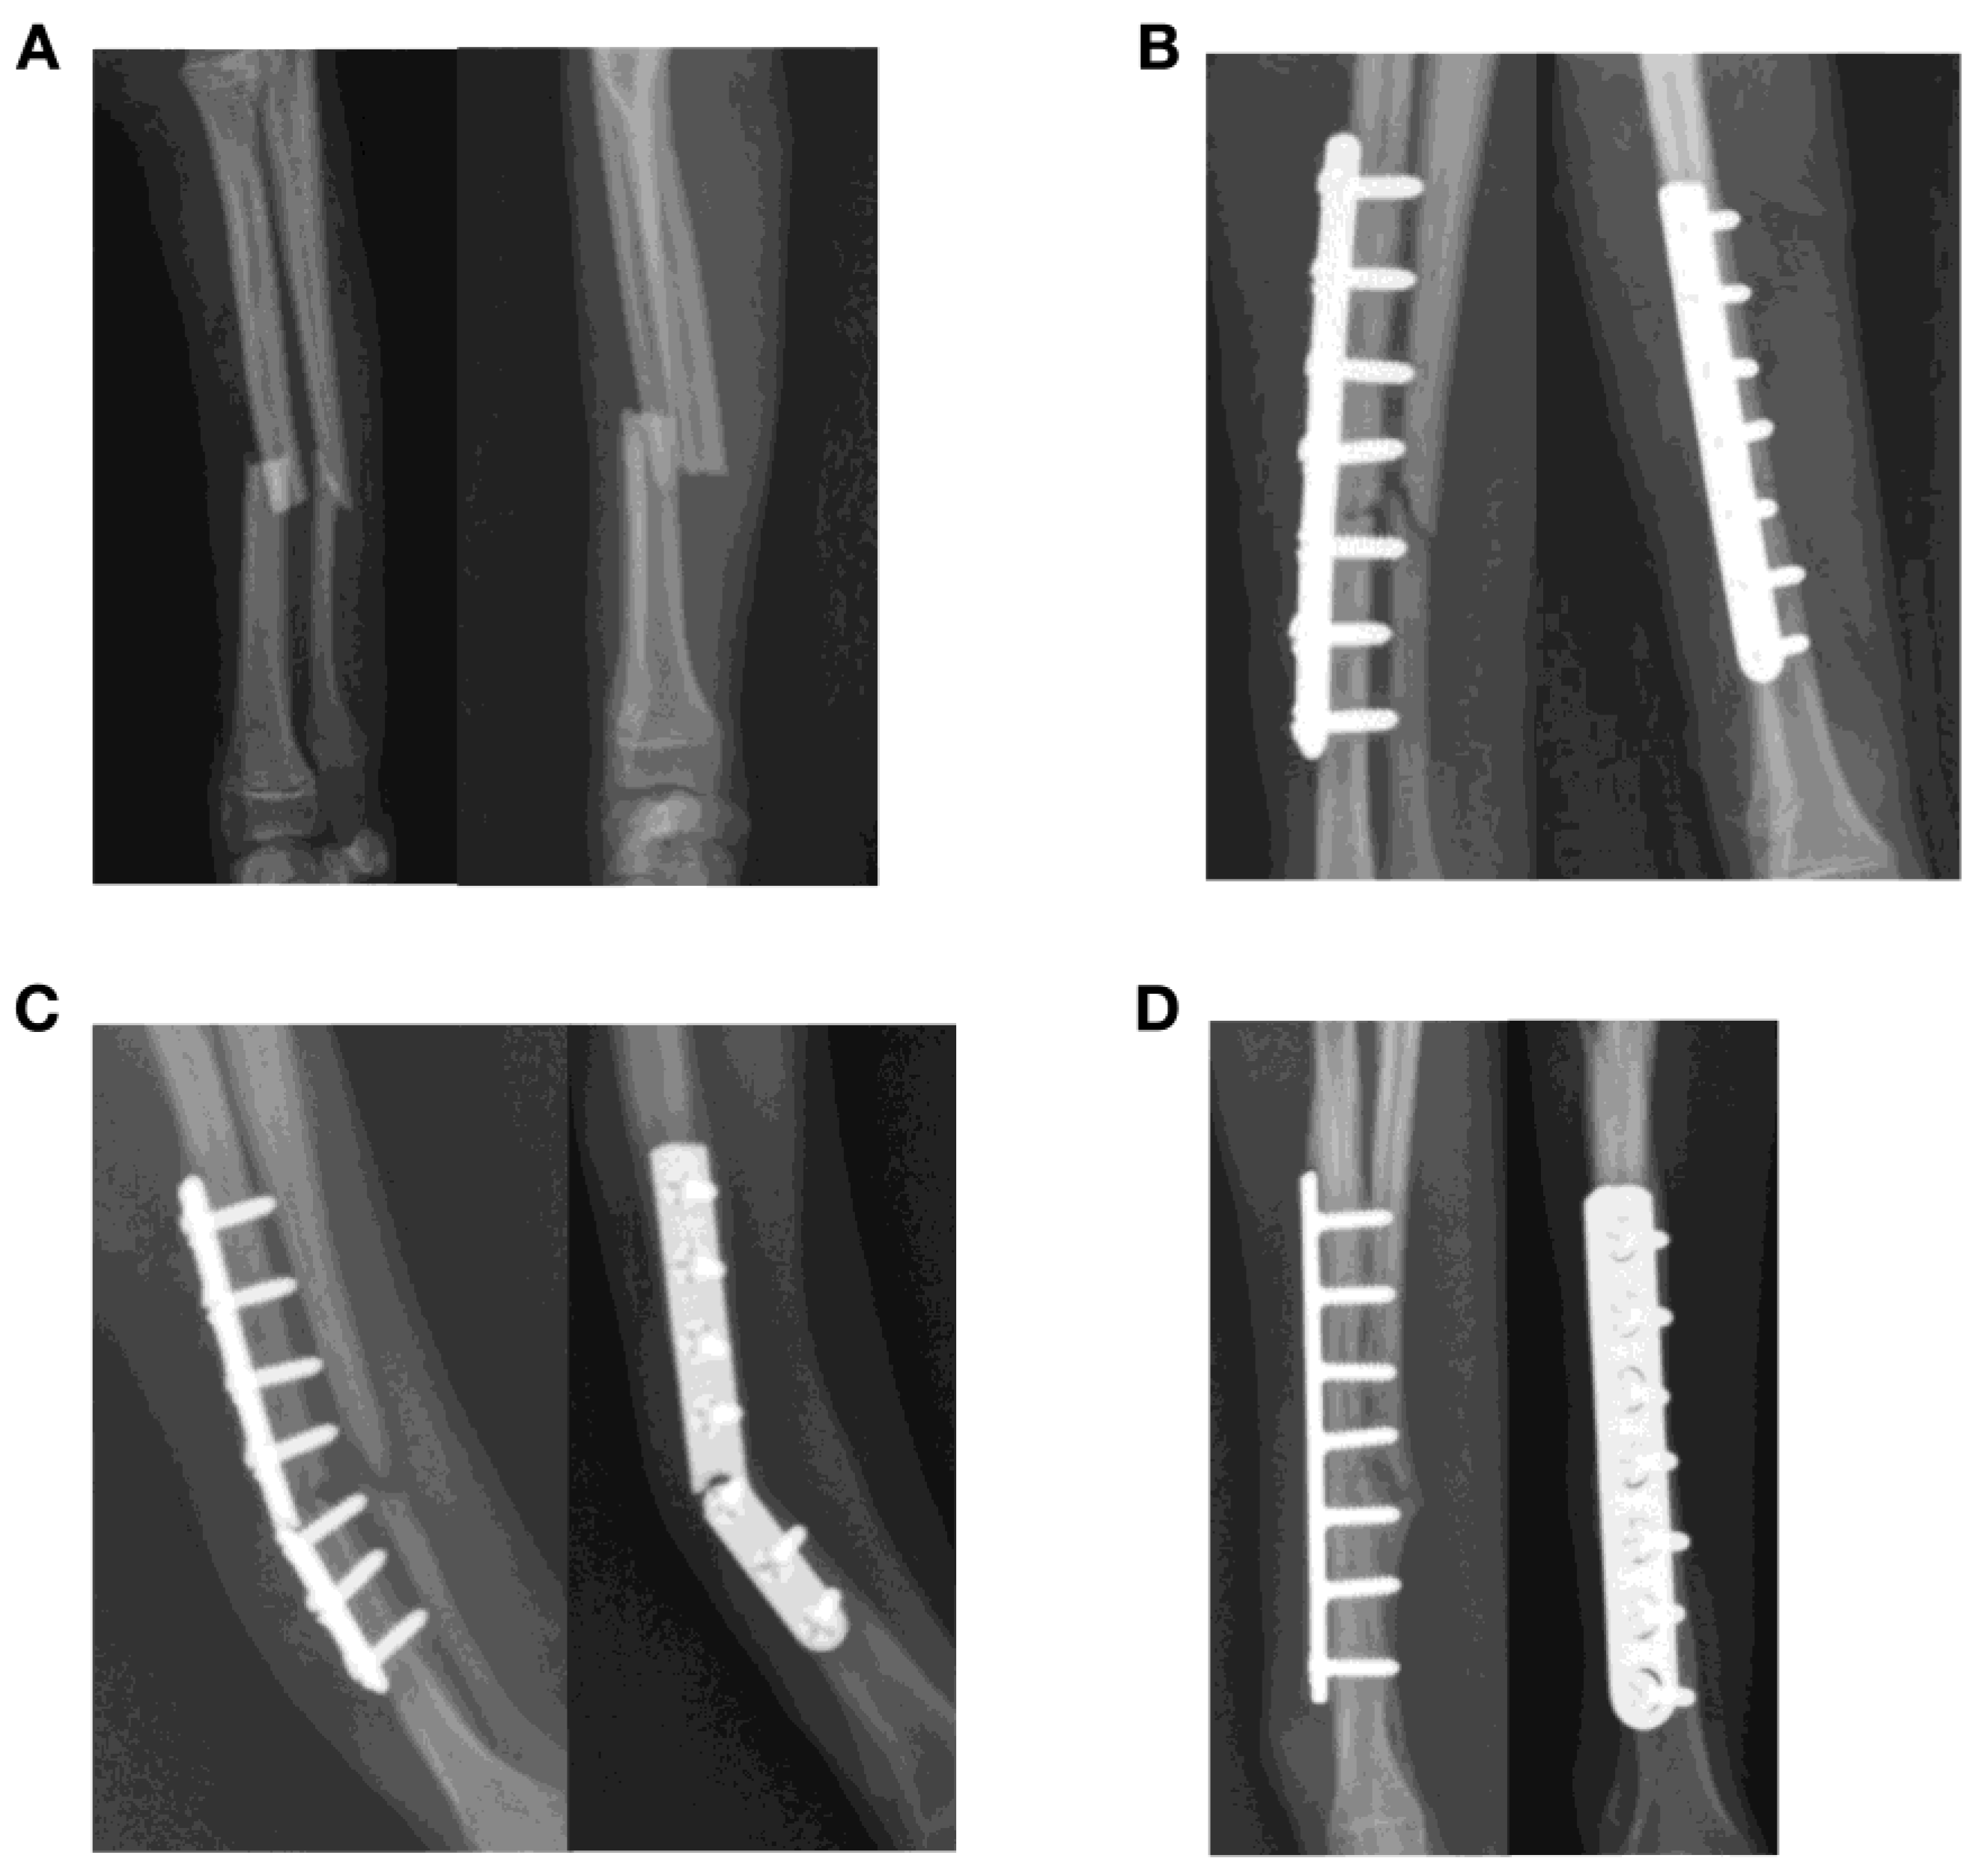

Figure 2.

Failure of a plate construct after treatment of a closed transverse fracture of the radius and ulna in a one-year-old Chihuahua. (A,B) The fracture was stabilized with a 7-hole 1.5 straight plate that did not permit interfragmentary compression, with four 1.5 mm cortical screws proximal and three 1.5 mm cortical screws distal to the fracture site. Autogenous cancellous bone graft was also applied to the fracture. (C) Plate breakage was found at 3 weeks after surgery at the level of the fracture. Although the implant was considered a neutralization plate, plate strain at the level of the fracture would be expected to be high after surgery as fracture reduction and the lack of interfragmentary compression left a small gap at the fracture site. (D) The fracture construct was revised with another 7-hole 1.5 mm straight plate. The final outcome was a delayed union after 70 days.